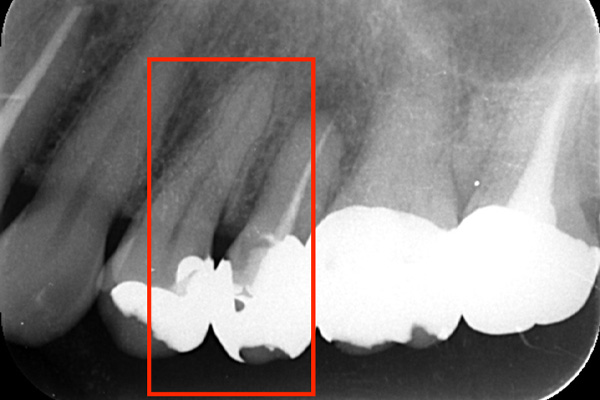

こちらの写真は違和感があるということでレントゲンを撮ったが異常は見つからなかった。しかし、1ヶ月後にもう一度撮影すると、歯が割れているのがわかりました。また、歯の周りの骨の部分がやや黒くなっているのも分かります。